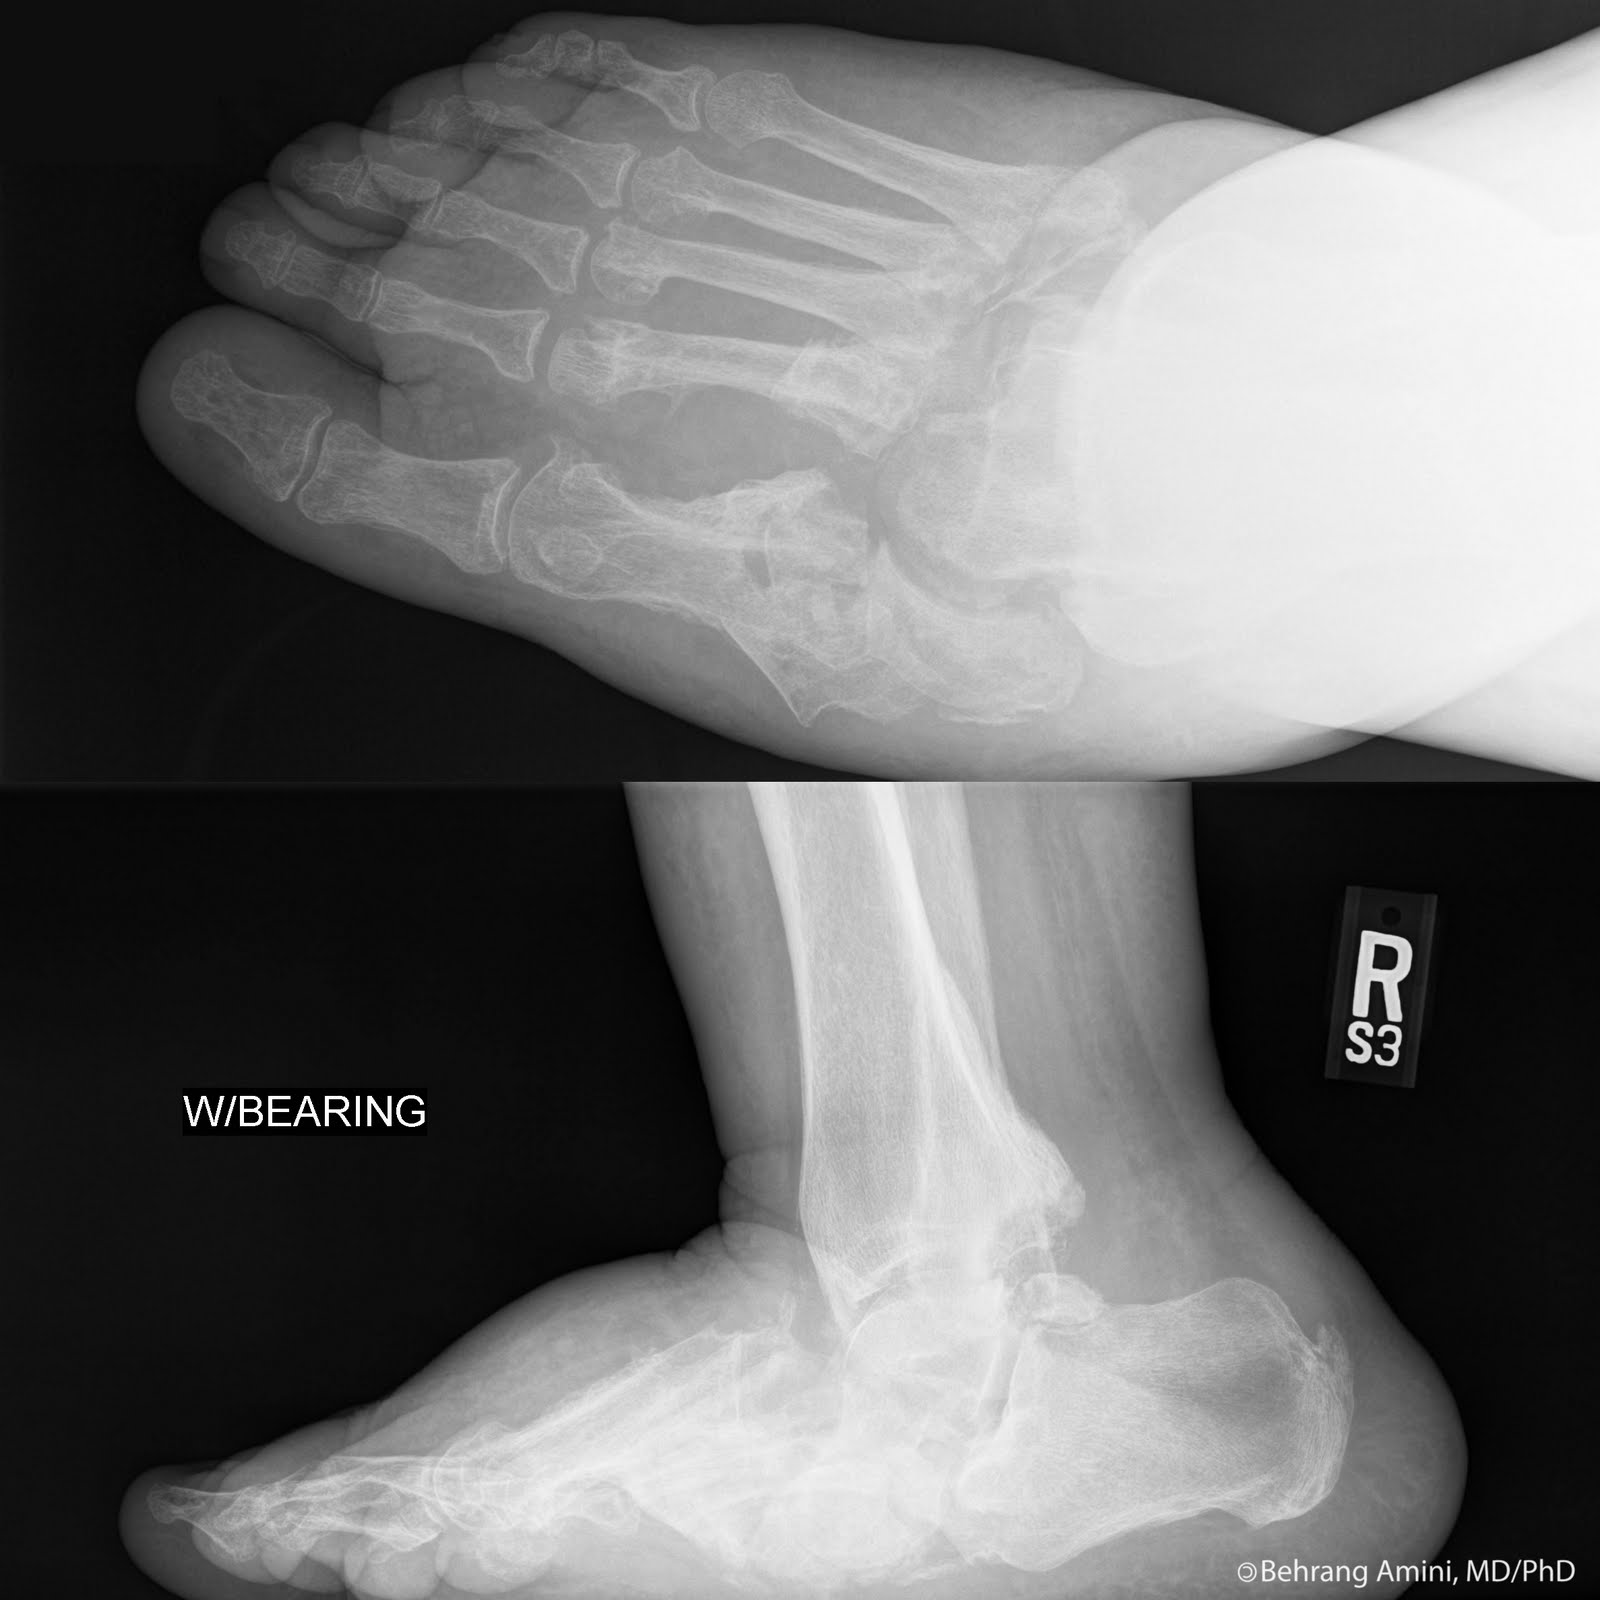

From orthopaedicprinciples.com

Neuropathic Joint — Foot Neuropathic Joint neuropathic arthropathy is a rapidly destructive arthropathy due to impaired pain perception and position sense, which can result from various underlying disorders, most commonly diabetes and stroke. Neuropathic arthritis is a condition that affects the joints and nerves. also called charcot joint or neuropathic joint, charcot arthropathy is a progressive condition of the musculoskeletal system that is characterized. Foot Neuropathic Joint.